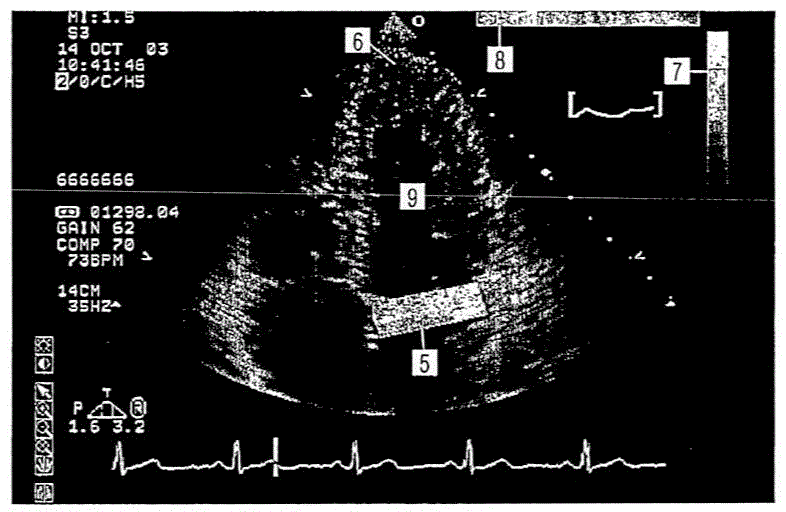

缺血性心脏病的超声诊断